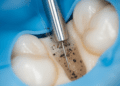

Conhecer a anatomia do dente é fundamental para o diagnóstico, tratamento e prevenção de doenças bucais. Procedimentos como obturações, canal radicular, próteses e ortodontia dependem do entendimento claro das características estruturais para serem eficazes.

Além disso, a anatomia dentária é essencial para a identificação dos dentes e suas funções, auxiliando o profissional na escolha de técnicas e materiais adequados segundo cada caso clínico.